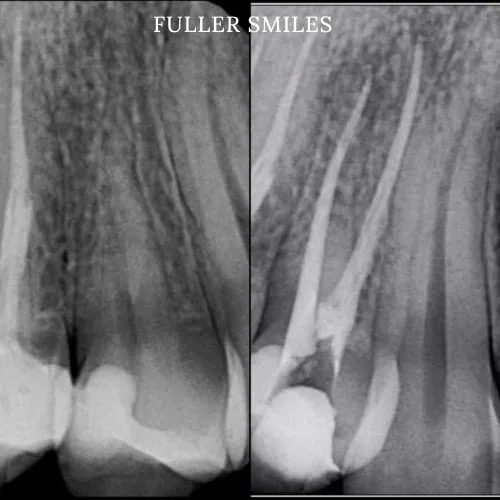

Patient presented with a complaint of severe constant pain that would exaggerate on laying down and biting. Patient wanted to save the tooth. A thorough clinical exam, endodontic screening and proper x rays led to the diagnosis of necrotic (dead) pulp due to dental caries with inflamed periodontal ligaments.

Our Dentists used the latest technology and highest quality products to finish this beautiful root canal. The tooth was crowned after the root canal to restore function and aesthetics.